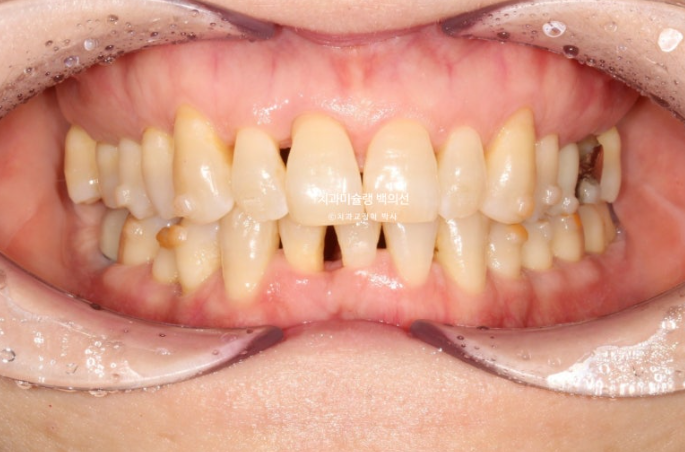

1년 전 치아 틀어짐이 점점 심해지면서 찾아오신 50대 환자분

예전에는 입이 편하게 다물어졌었는데 치아가 틀어지고 벌어지고 내려오면서 이제는 입이 편하게 안 다물어지는 것도 불편한 상태입니다.

위 앞니는 잇몸이 꽉 잡아주지를 못해서 점점 솟아 내려오고 튀어나오면서 치아사이가 벌어졌습니다.

작은어금니도 안으로 쓰러져 있어서 이 부분은 윗니와 엇갈려 물리는 가위교합 입니다.

앞니가 깊게 물리는 과개교합이 개선되었습니다.

특히 뿌리가 보일 정도로 솟아내려와있던 파란 화살표 앞니가 건강하게 제 위치로 함입이 되고 노출된 뿌리 부분이 다시 잇몸속으로 안정적으로 들어갔습니다.